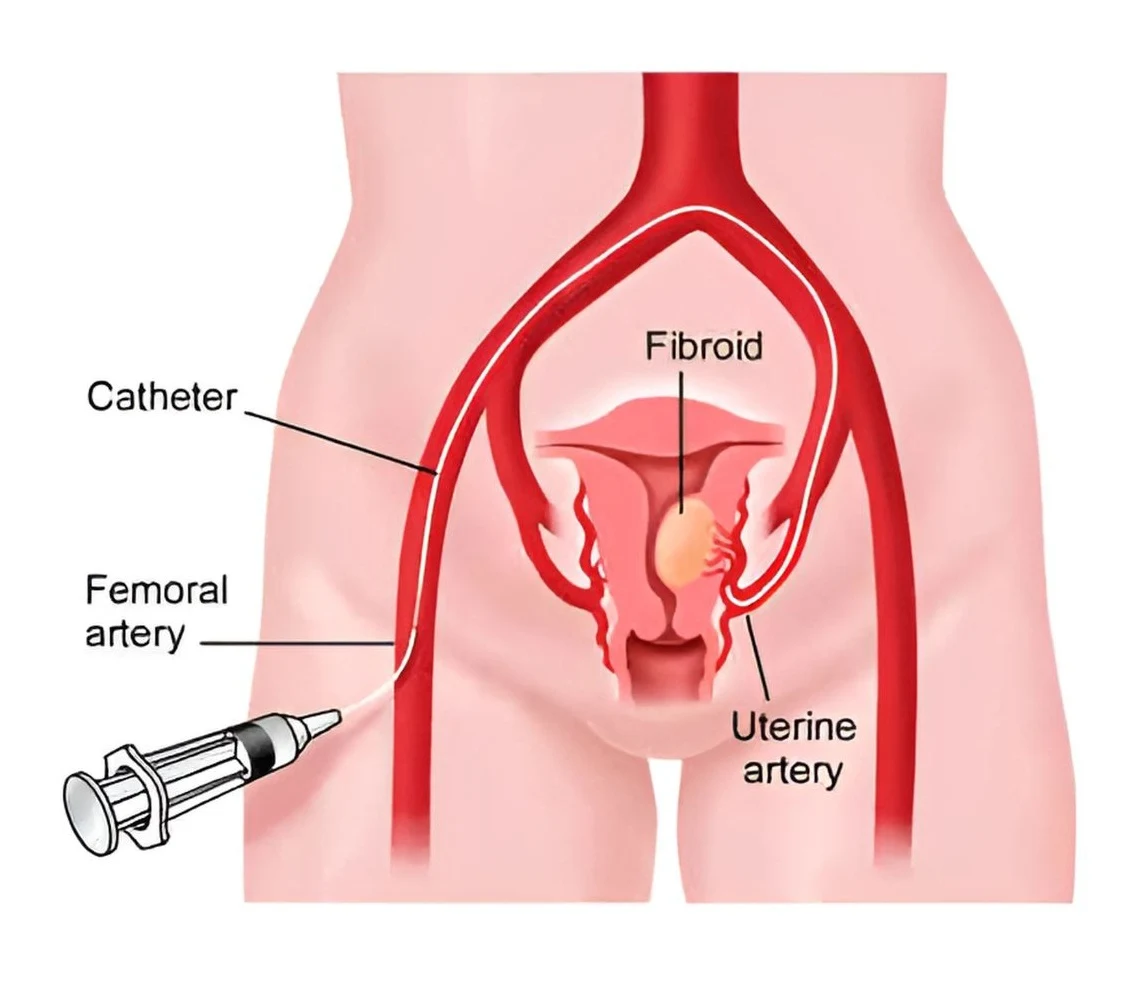

In UAE, imaging is done by a Vascular and Interventional Radiologist. This procedure differs from surgery, where large cuts are made to physically remove tissue. For Uterine Artery Embolization, a small puncture and a thin instrument called a catheter are employed. The procedure aims to regulate blood flow. This is achieved through the uterine arteries, whose function is to deal with the condition causing symptoms. Dr. Rakesh Kumar Kumawat is greatly trusted for his work involving minimally invasive methods since he is a proponent of precision medicine. Indeed, if a woman’s life is impacted due to her period of bleeding and pain and/or pressure symptom due to a possible ovarian cyst, not only should she find relief, but it should happen in a manner that is convenient to her.

In the UAE treatment, imaging guidance is utilized to ensure the catheter passes safely through blood vessels to reach the precise area of the uterine arteries. Smaller particles are finally infused to lower blood supply for the specified areas of the uterus. Over the period, the body compensates for the foreign matter by shrinking the sizes of the fibroids or adjusting the bleeding patterns.

Step 3: Access and Catheter Navigation A small puncture is made, most commonly in the groin, but sometimes the wrist is preferred depending on technique and preference. A smaller catheter is then introduced into the artery under imaging guidance to go to the uterine arteries.

Step 4: Embolization (Reduction of Blood Flow) Embolic particles are injected through the catheter to decrease blood flow to the selected branches of the uterine artery. This is the definitive step. For fibroids, reduced blood flow causes fibroids to shrink gradually. Reducing blood flow will assist in stopping the bleeding in cases of postpartum hemorrhage.